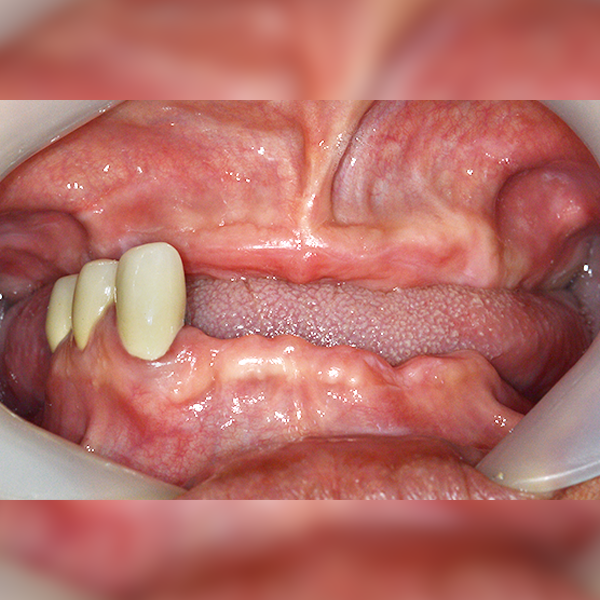

Nha khoa One Day

Toàn hàm/Toàn bộ / Ghép xương | Tiền mê | Tiểu đường

Trường hợp 41. U40 Lee*joon 2020-06-26 / 2021-01-17